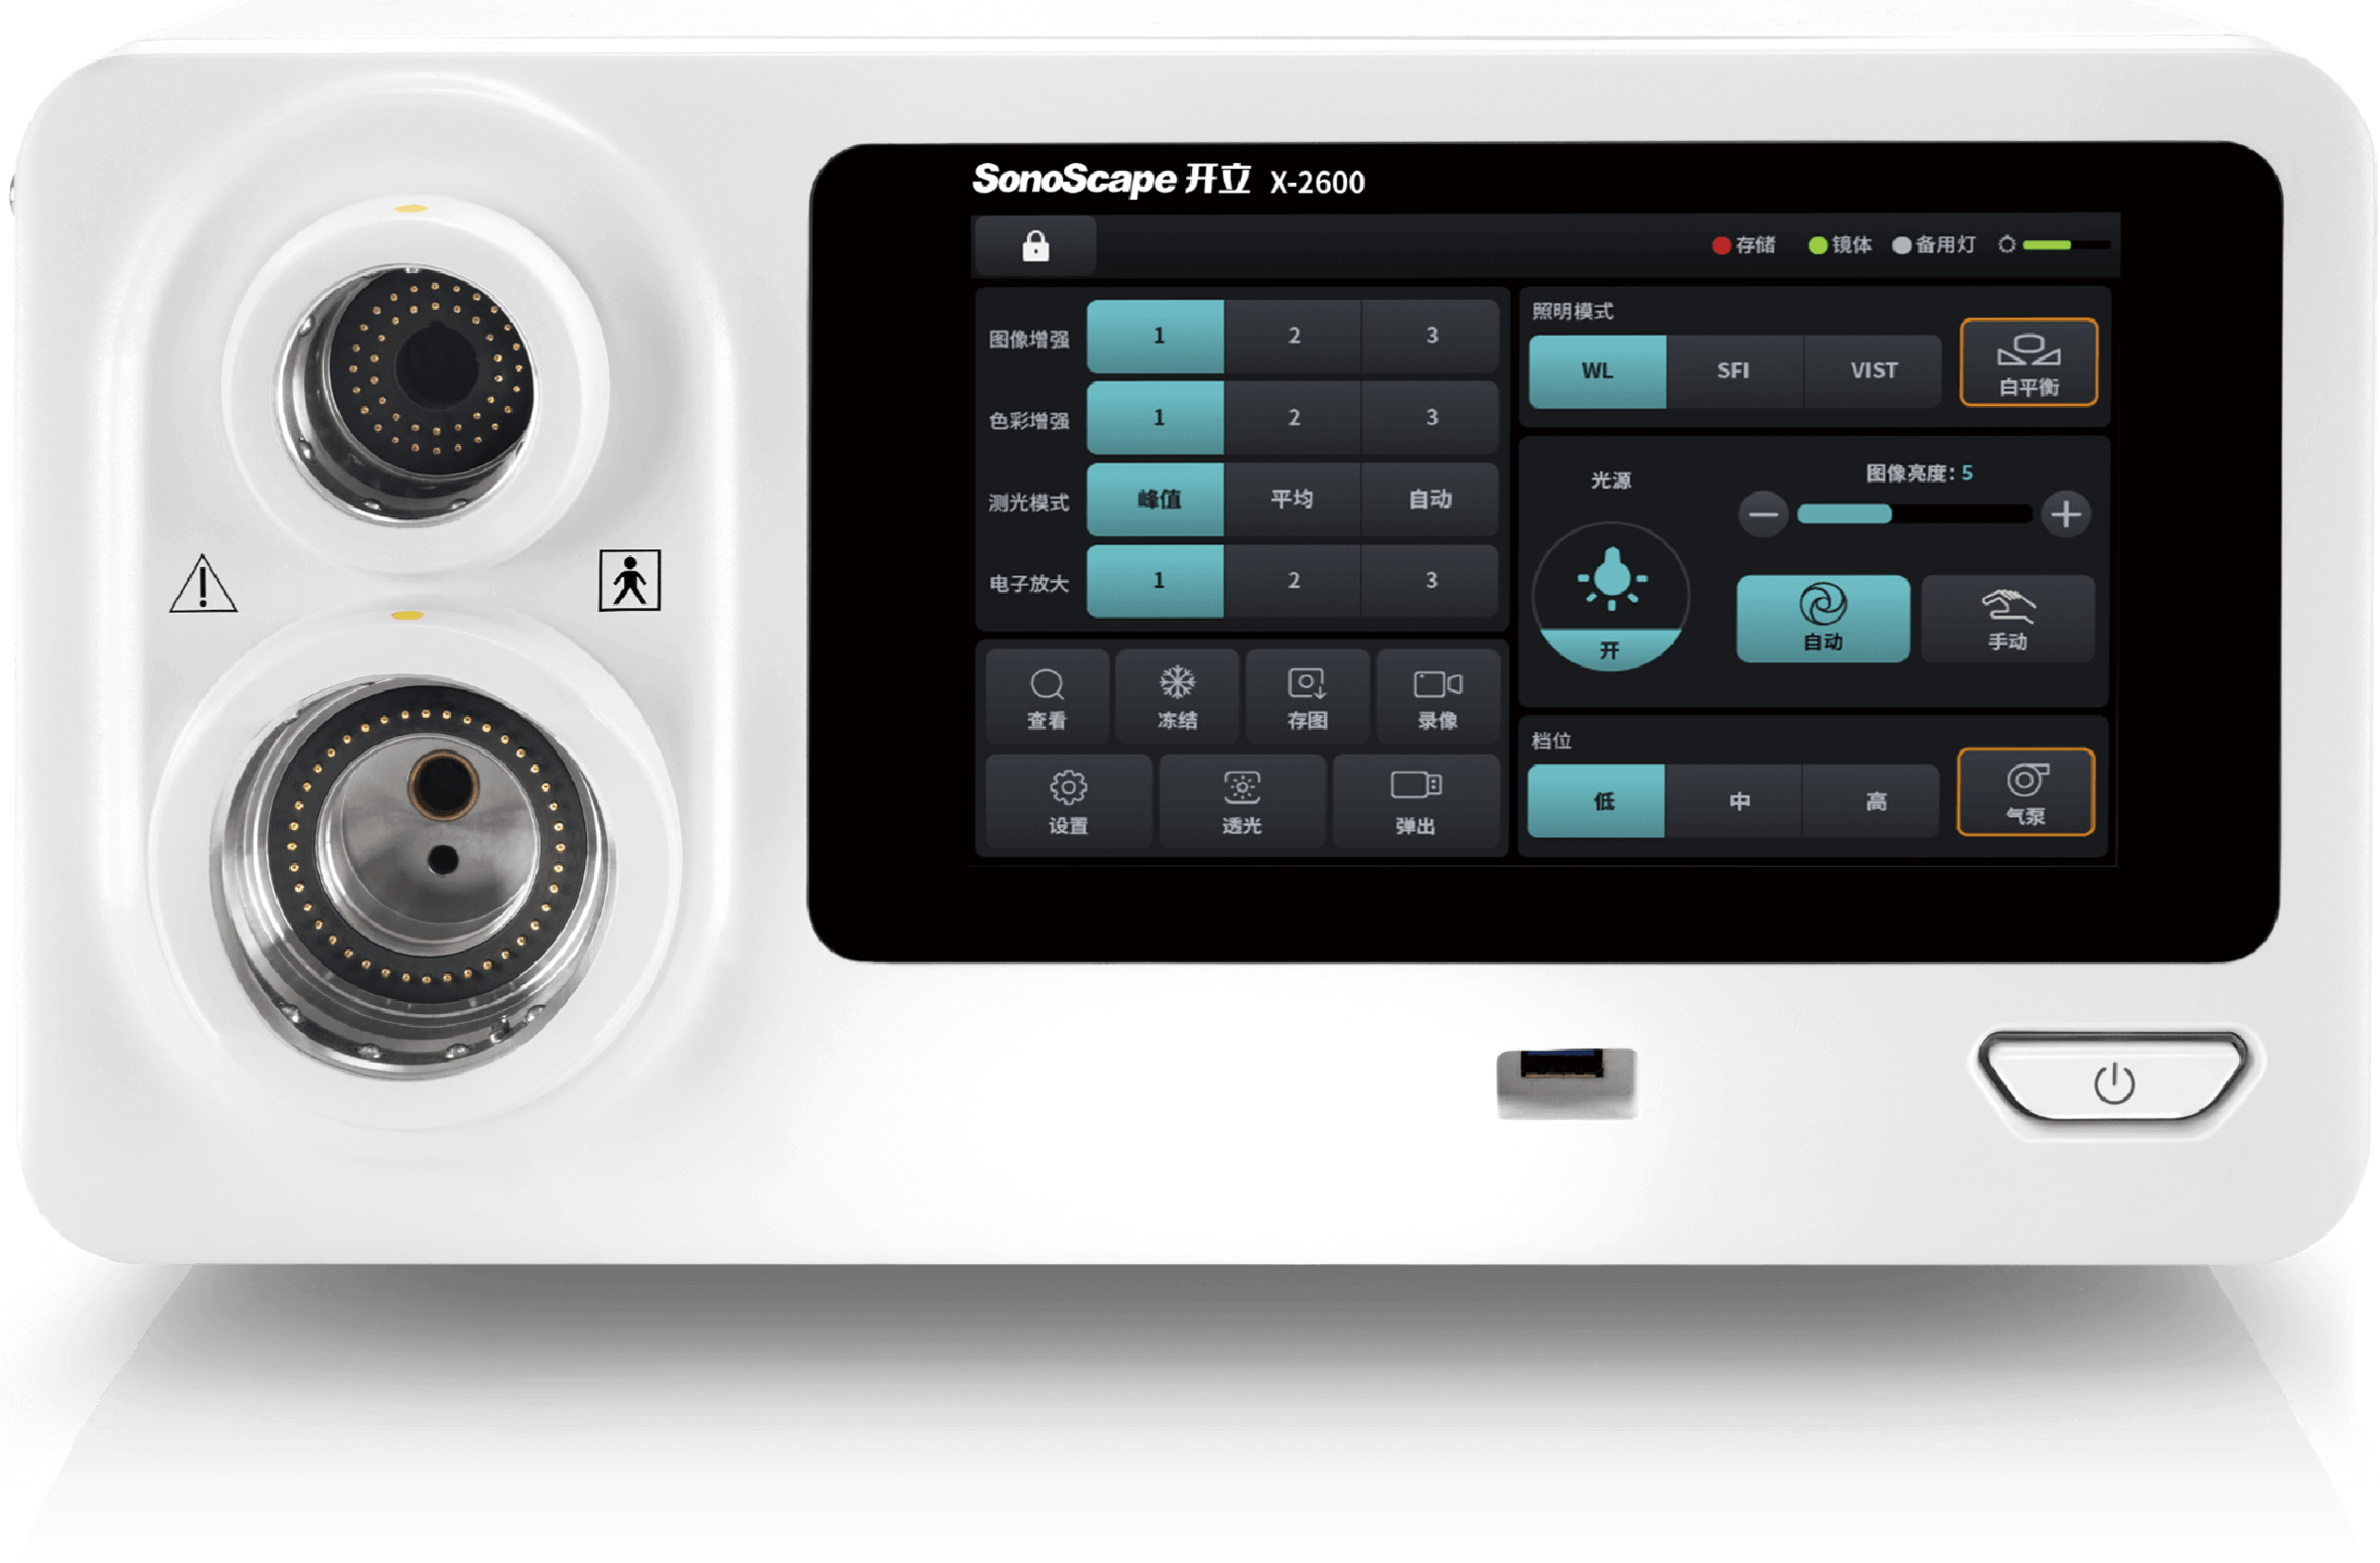

主机前面板为触摸屏,用户可以轻松调节各种参数,选择所需的功能,极大地提高了使用的便利性。

智能锁键 防止误触

软镜、硬镜独有界面 根据镜体智能识别

软镜UI界面 硬镜UI界面